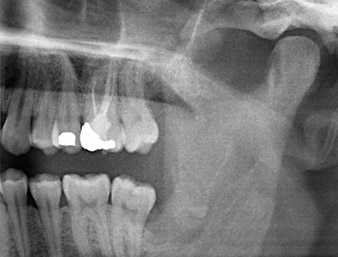

The root remnant in the region of tooth 38 (LL8) was already displaying close proximity to the inferior alveolar nerve on the OPG. The root had fractured during the osteotomy but had not been removed by the primary treatment provider due to intraoperative pain. To ensure as little trauma as possible to the tissue, the new osteotomy was to be carried out using a piezo surgical system. The patient had an unremarkable medical history and was a non-smoker.

OPG 6 months after osteotomy

Fig. 1: OPG 6 months after osteotomy of tooth 38 (LL8): radix relicta lies close to the inferior alveolar nerve.

It could be seen in the 3D image (digital volume tomography) that the root remnant was located disto-caudally in the transition from the horizontal to the ascending portion of the mandible (Fig. 2).